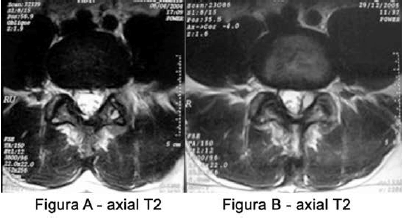

Um paciente de 55 anos apresentou início de lombalgia em 04/2004, quando realizou exame de RM que revelou alterações degenerativas (Figura A). Ele relata que, no final de 2005, a dor mudou de características e passou a irradiar para o MIE, tendo realizado novo exame de RM (Figuras B, C, D).

Após a análise das imagens de RM acima, o diagnóstico da causa da dor do paciente é: